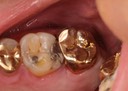

Joe Cha #18 pre-cementation

Joe Cha #18 finish